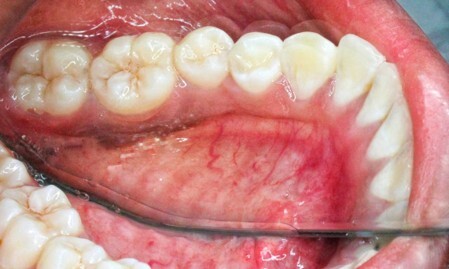

Fig 4 through Fig 6. Lingual attached gingiva in a male subject: Fig 4 = left side.

Figure 4

Fig 5 = middle.

Figure 5

Fig 6 = right side.

Figure 6

Table 1 presents descriptive statistics for the demographic characteristics of the participants: 83.33% of the study population were aged 18 to 24 years, while 16.66% were aged 25 to 30 years, and 20% of the participants were male while 80% were female, indicating a skewed distribution. Figure 4 through Figure 6 illustrate lingual AG of a representative male subject, and Figure 7 through Figure 9 depict that of a female subject. The mean, standard deviation, mode, median, and extremes for all the mandibular permanent teeth are recorded in Table 2. The extreme measurements were in the range of 0 mm to 10 mm, considering all teeth and subjects. The width of lingual AG varied with each tooth, with the mandibular first molar having the widest average width (6 mm ± 1.3 mm) followed closely by the second molar (5.8 mm ± 1.2 mm). The central incisors (0.5 mm ± 0.5 mm) showed the narrowest zone along with the highest maximum number of teeth without detectable AG (Table 3). The width of AG did not significantly differ between the sexes (Table 4). The overall indicative schematic of lingual AG is shown in Figure 10 and Figure 11.